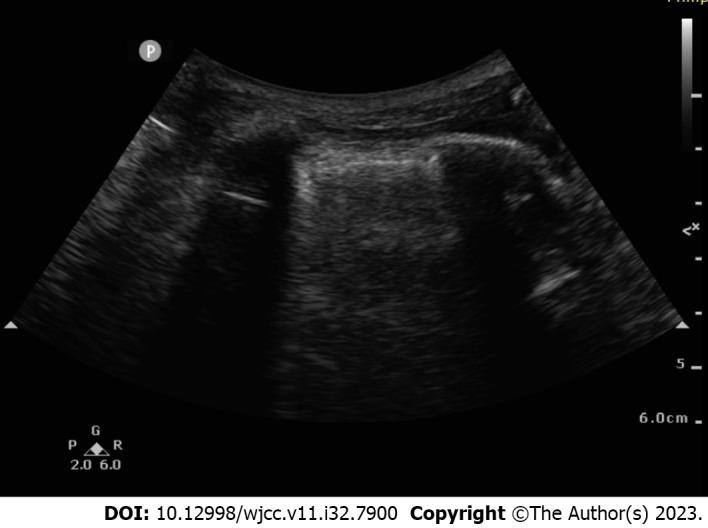

We report a patient under anaesthesia whose lung US examination showed multiple vertical artefacts (B-lines) in the lung tissue, indicating pulmonary oedema. The respiratory state improved with the resolution of the pulmonary oedema after our treatment.

我们报告了一名麻醉患者,其肺部超声检查显示肺组织中有多个垂直伪像(B线),提示肺水肿。经过我们的治疗,随着肺水肿的消退,呼吸状态得到改善。